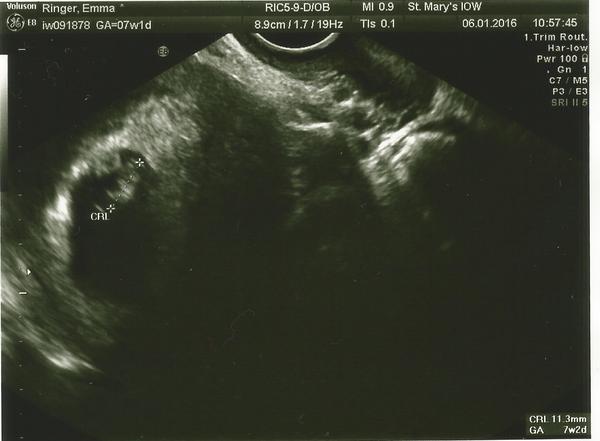

Here you go ladies. My little tadpole over on the left

Lovely squiggle - I measured 7and 2 today as well! Makes it seem all the more real when that picture flickers up on screen, doesn't it?

Btw your name and details are on the pic at the top - just in case you want to keep your anonymity!

Ahh squiggle that's fab! My scan at that stage literally just looked like a blob, yours is super clear!